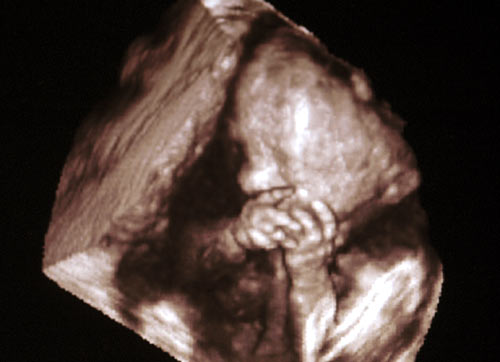

Transvaginal ultrasonografi ile gebelik kesesi ( gestasyonel sac) rahim içinde saptanabilir. Gebelik kesesi genel olarak 4 hafta+3 gün gibi erken bir dönemde saptanabilir. Rahim iç duvarında 3-5 mmlik içi koyu renkli halka şeklinde gözlenir.

Gebelik kesesi (gestasyonel sac) artık transvaginal ultrasonla 5.haftada mutlaka rahim içinde görülmelidir.Yaklaşık 1 cm büyüklüğe ulaşır. Bu esnada kanda gebelik testi B-HCG 1500-2400 civarındadır. Gebelik kesesi kalınlaşmış rahim iç duvarı içinde yaklaşık 8-10 mm boyutunda koyu renkli bir halka şeklinde görülür ve günde 1-2 mm büyür. Gebelik kesesi yaklaşık 1 cm büyüklüğe ulaştığında yolc sac da görünmeye başlar. Ortalama 1.5 cm çaplı gebelik kese içinde embrio ve yolc sac birlikte görülür.

Bu dönemde çok hızlı bir büyüme ve değişim söz konusudur. Bebeğinizin kalp atımları transvaginal ultrasonla saptanır. Doppler ultrasonla duyulabilir.

Fetus artık hem vaginal hemde abdominal( karın) ultrasonografi ile rahatlıkla değerlendirilebilir. Baş-popo uzunluğu yaklaşık 2 ila 3 cm’dir. Embrio insan şeklini kazanmıştır. Ultrasonda baş, gövde ve ekstremiteler saptanabilir. Bebeğin kol-bacak ve vücut hareketleri ultrasonda görülebilir. Fetus ekstremitelerini ve gövdesini kımıldatmaya başlar ve rahim içinde takla atarken görülebilir. Ancak anne bunu hissedemez. Cinsiyeti görebilmek mümkün değildir.